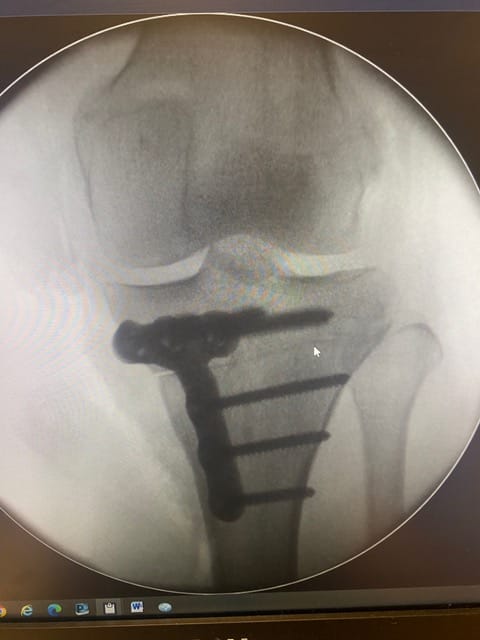

Bodycad has transformed the accuracy and success of this operation. It offers 3D analysis of the patient’s pre-op situation, patient-specific instrument and plate design, 3D printed bone models, personalized surgical guides, and personalized plate solutions. This patient specific design leads to better accuracy and outcomes.

In this case, a young patient had knee pain due to deformity in the tibia. This occurred secondary to a fracture that had disturbed their growth plates as a child. The accuracy of the correction that BC Fine Osteotomy achieved is fantastic and should allow a return to pain free function.